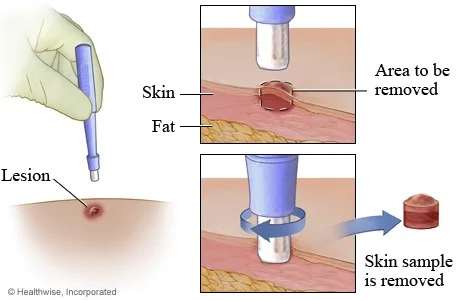

اگر گرهها کوچک نشوند یا به رشد خود ادامه دهند، یک گره لنفاوی (یا یک قطعه کوچک از یک گره) خارج میشود تا در آزمایشگاه بررسی شود. این روش که بیوپسی نام دارد، تنها راه برای اطمینان از تشخیص است. اگر HL باشد، بیوپسی نیز میتواند نوع آن را نشان دهد.

بیوپسی اکسیزیونال (Excisional biopsy) یا برشی (incisional biopsy): این نوع بیوپسی ترجیحی و رایج برای بزرگ شدن غدد لنفاوی است. پزشک برای برداشتن غده لنفاوی پوست را برش میدهد.

- اگر کل غدد لنفاوی برداشته شود، بیوپسی اکسیزیونال است.

- اگر قسمت کوچکی از تومور یا گره بزرگتر برداشته شود، بیوپسی برشی است.

اگر گره درست زیر پوست باشد، بیوپسی نسبتاً ساده است و گاهی اوقات میتوان با داروهای بی حس کننده (به نام بی حسی موضعی) آن را انجام داد اما اگر گره داخل قفسه سینه یا شکم (belly) باشد، داروی آرام بخش به شما داده میشود یا تحت بیهوشی عمومی (که در آن از داروها برای خواب عمیق استفاده میشود) قرار میگیرید. این نوع بیوپسی تقریباً همیشه بافت کافی برای تشخیص HL و تشخیص نوع دقیق را فراهم میکند.